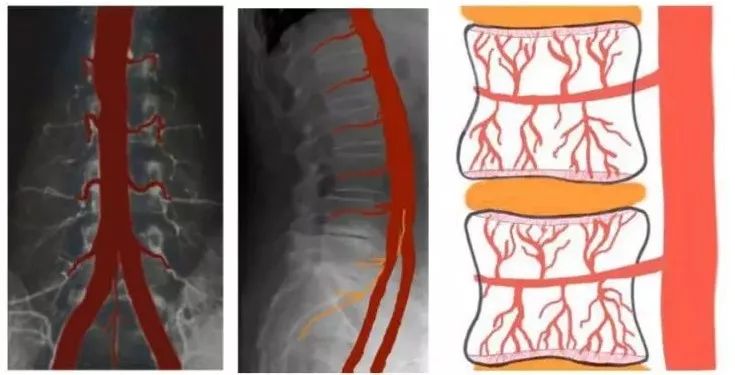

这张图反映的是,腰椎间盘的供血情况。

主动脉下行途中,在每一节腰椎的位置发出一对侧枝,即椎动脉。椎动脉不断分支,最终的细小血管向椎间盘供应血液。

在上图的X光图中,左边正常人的腰椎骨之间被健康的结缔组织分开(两节椎骨间黑色的部分)[10]。

右边腰椎间盘退化的人,腰椎骨间已经变白了,这意味着腰椎间盘的软组织已经钙化了,失去缓冲了。

对应动脉造影,正常人的椎动脉非常清楚;病人的椎动脉已经堵死,难以供应血液了。